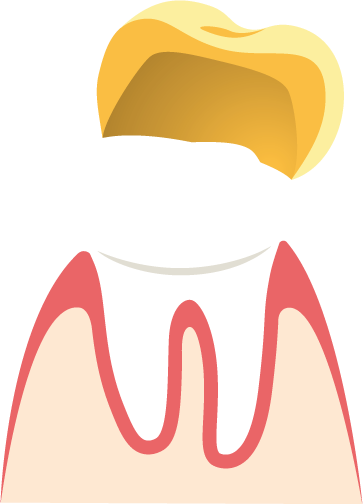

Aufbau einer künstlichen Krone